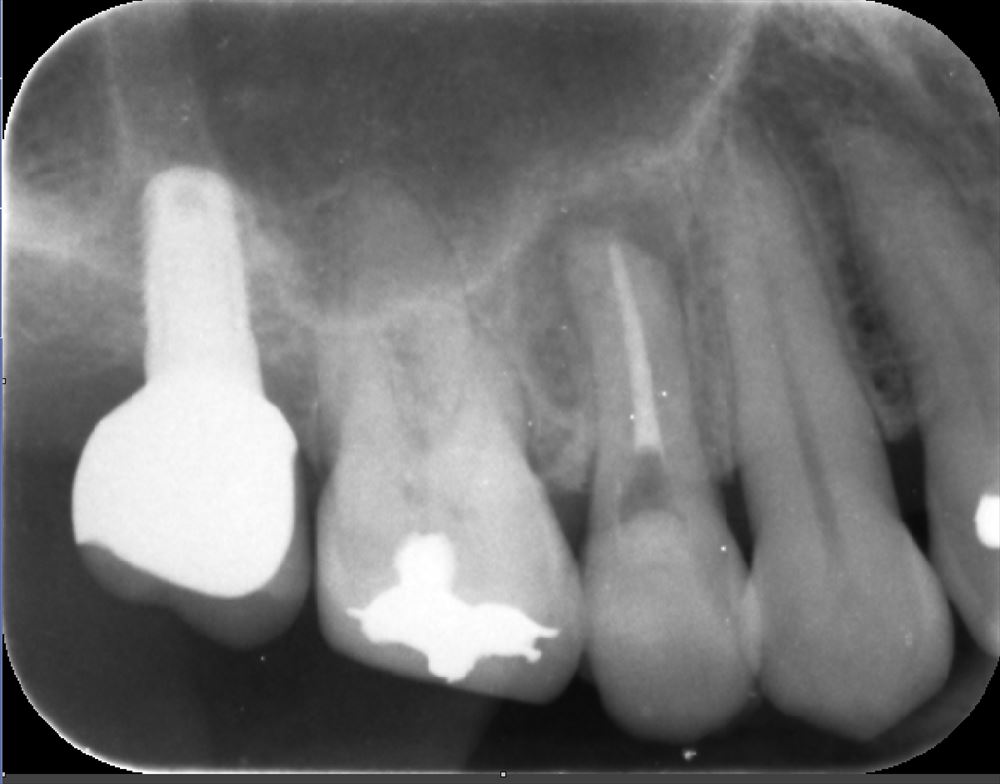

術前は感染だらけ

症状もなくレントゲンでも問題ありませんでした。

術前(右)根管充填後(左)